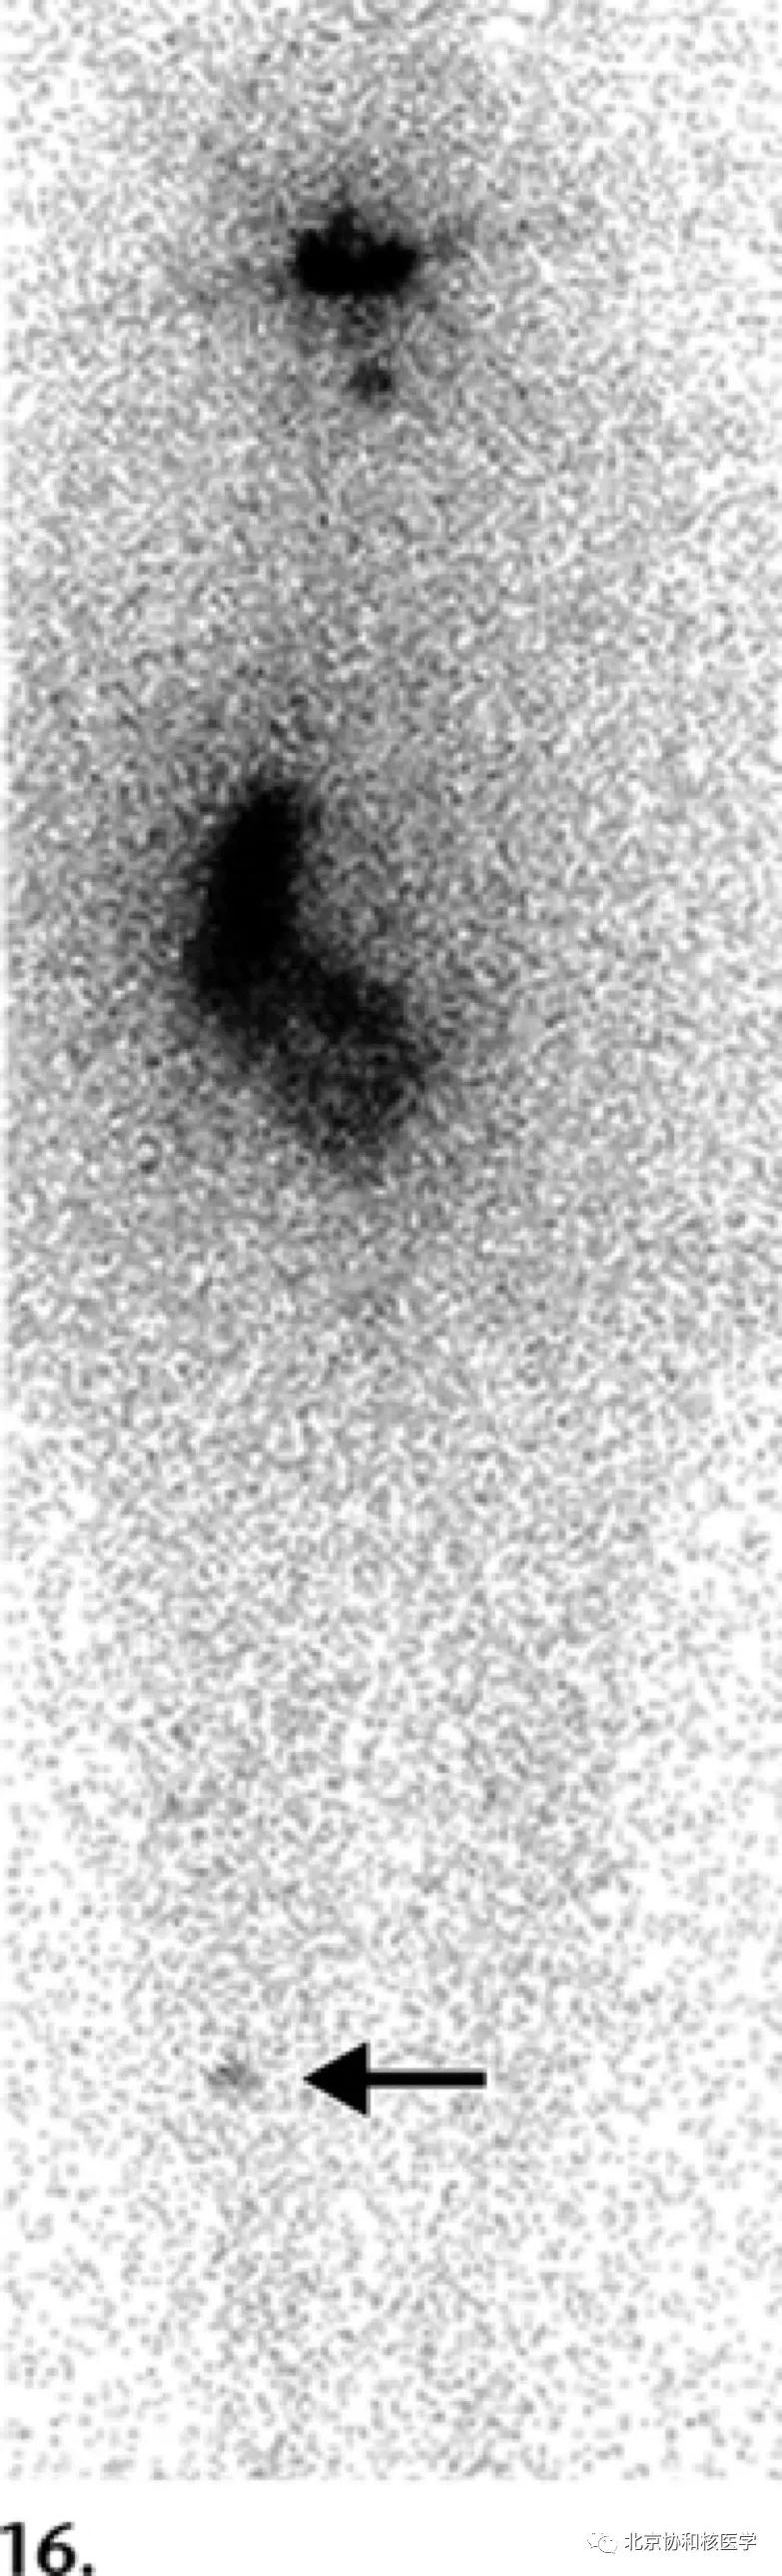

72岁男性,甲状腺全切术后(乳头状癌),碘131治疗后碘扫见鼻腔分泌物所致摄取:

鼻腔脓肿所致碘摄取,其下方可见颈部残余甲状腺: